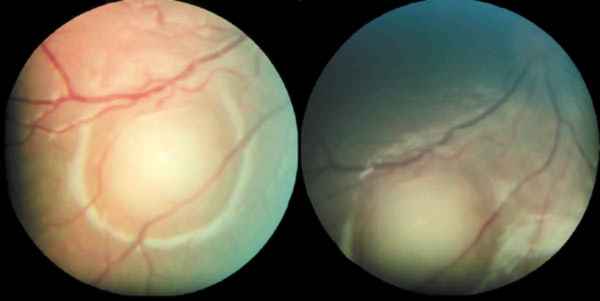

Paz.    Figura 1.  Retinoblastomas masivos. Diversos tipos de manifestaciones que

producen síndromes de enmascaramiento.